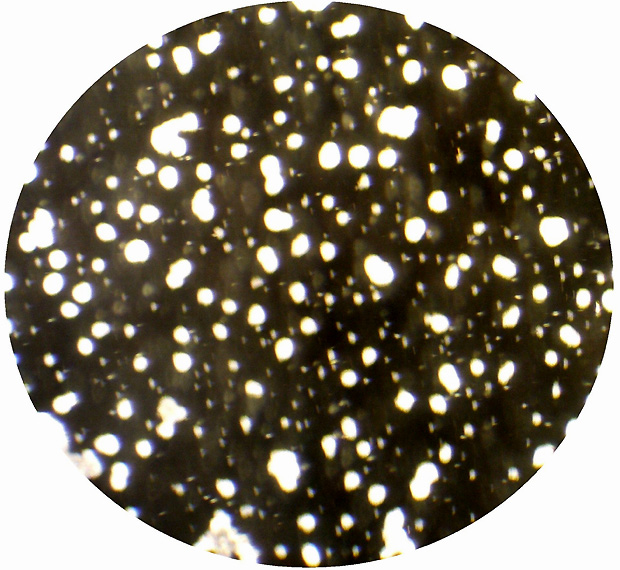

Als Standardmethode zur Diagnose der Leptospirose dient der Nachweis der von infizierten Menschen oder Tieren gebildeten Antikörper mittels Mikroagglutinationstest (MAT). Bei dem MAT werden die Seren der Patienten verdünnt und mit lebenden Leptospirenstämmen versetzt; beim Vorhandensein von Antikörpern kommt es zu Reaktionen (Verklumpungen) der Leptospiren, die mikroskopisch beurteilt werden (siehe Abbildungen).

Lebende Leptospiren im Dunkelfeldmikroskop (Vergrößerung 1:500)